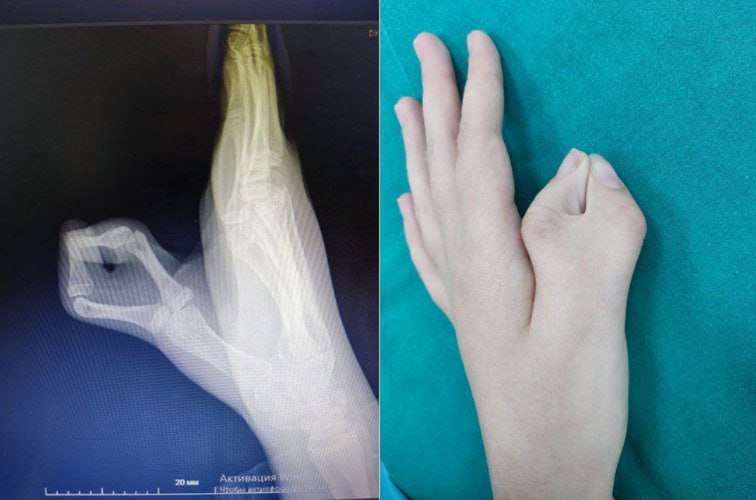

В ОКБ №2 обратились родители 12-летней девочки с врожденной особенностью — лишним пальцем на кисти.

Как объяснил кистевой хирург Игорь Супрунов, во время вмешательства медики не просто убрали добавочный палец, но и восстановили форму кисти, укрепив сустав спицей. Это позволит избежать повторной деформации пальца.

Лечение прошло успешно: через две недели сняли швы, а через полтора месяца рентген подтвердил, что фаланга полностью срослась.

Фото: Департамент здравоохранения Тюменской области